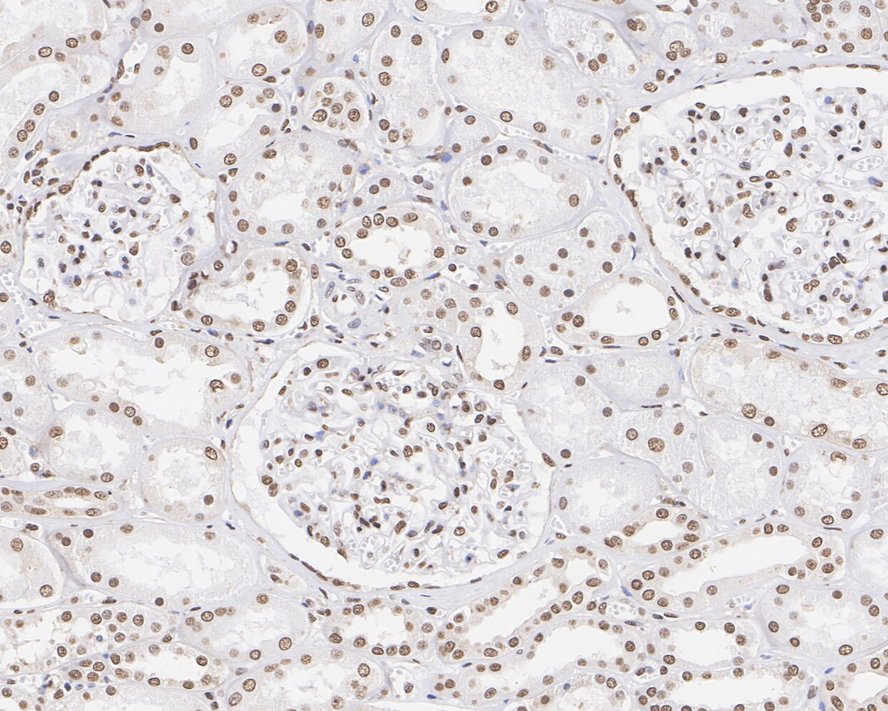

Immunohistochemical analysis of paraffin-embedded mouse kidney tissue with Rabbit anti-Pax2 antibody (ET7110-57) at 1/1,000 dilution.

The section was pre-treated using heat mediated antigen retrieval with sodium citrate buffer (pH 6.0) (high pressure) for 2 minutes. The tissues were blocked in 1% BSA for 20 minutes at room temperature, washed with ddH2O and PBS, and then probed with the primary antibody (ET7110-57) at 1/1,000 dilution for 1 hour at room temperature. The detection was performed using an HRP conjugated compact polymer system. DAB was used as the chromogen. Tissues were counterstained with hematoxylin and mounted with DPX.